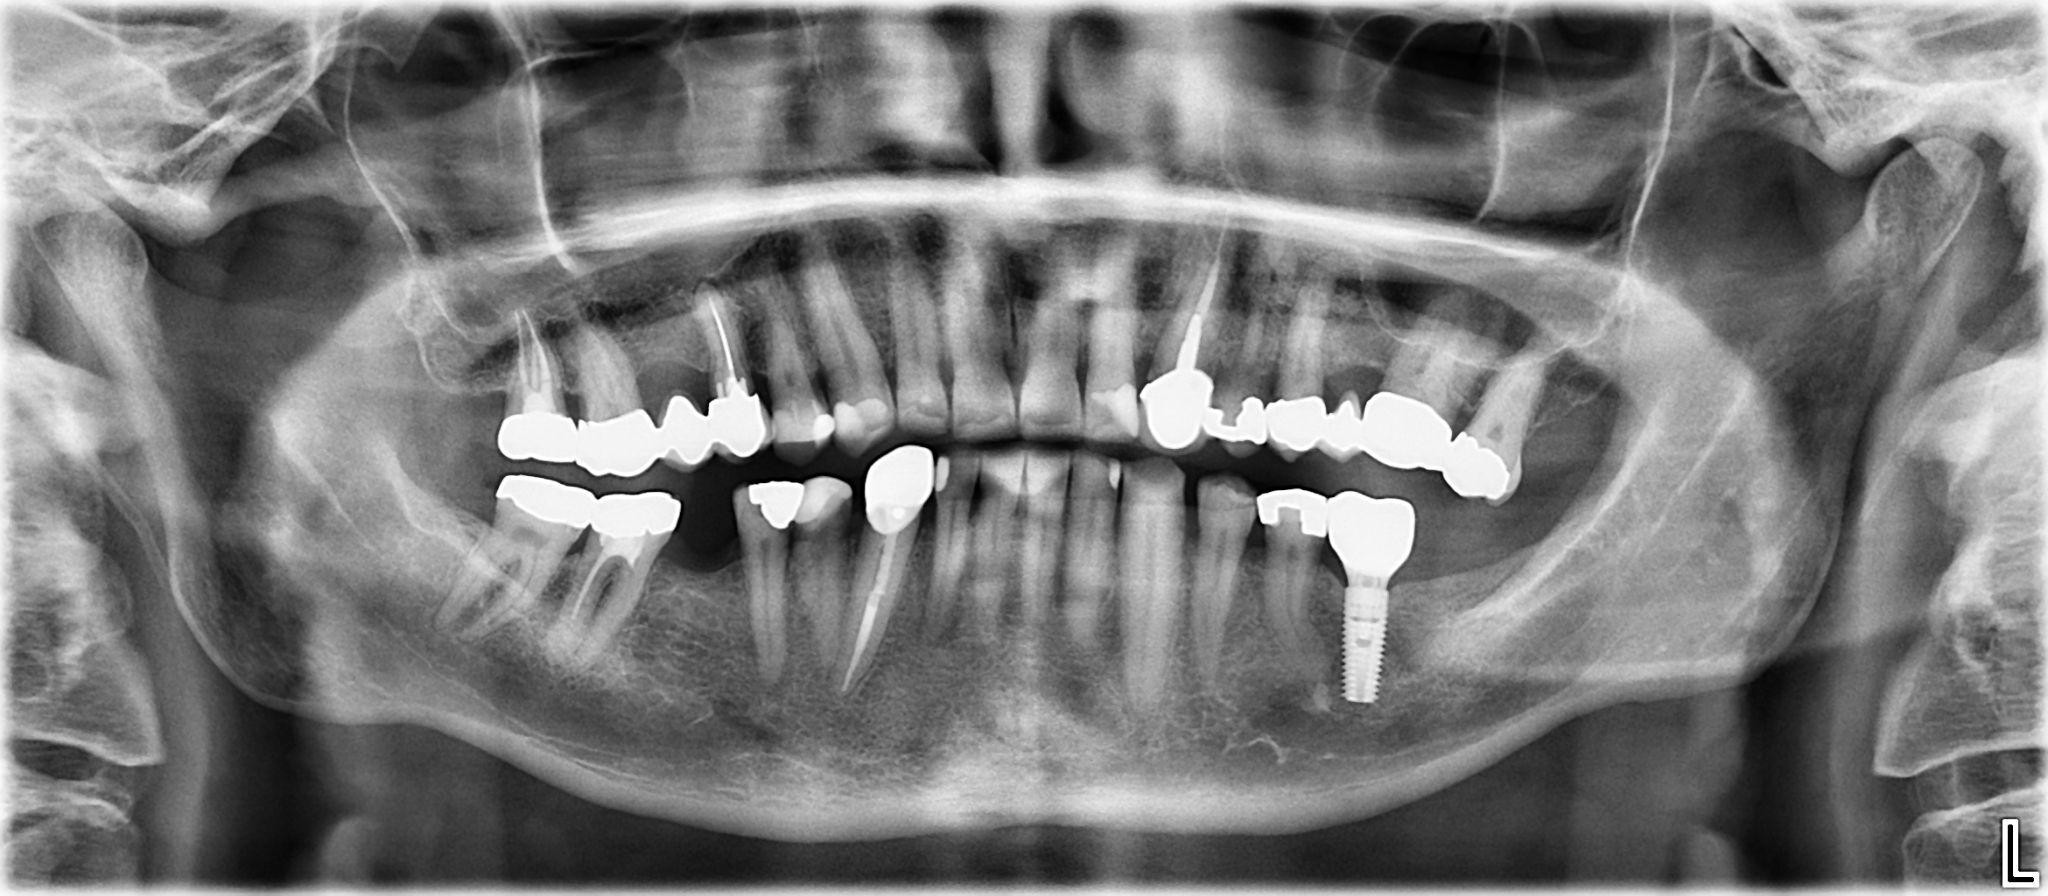

14 / 25

14. What option cannot be selected for the upper jaw of this panoramic X ray?

15 / 25

15. What option cannot be selected for the lower jaw of this panoramic X ray?

16 / 25

16. What option cannot be selected for the upper jaw of this panoramic X ray?

17 / 25

17. What option cannot be selected for the lower jaw of this panoramic X ray?

18 / 25

18. What option cannot be selected for the upper jaw of this panoramic X ray?

19 / 25

19. What option cannot be selected for the lower jaw of this panoramic X ray?

20 / 25

20. What option can be selected for the upper jaw of this panoramic X ray?

21 / 25

21. What option cannot be selected for the lower jaw of this panoramic X ray?

22 / 25

22. What option cannot be selected for the upper jaw of this panoramic X ray?

23 / 25

23. What option cannot be selected for the lower jaw of this panoramic X ray?

24 / 25

24. What option cannot be selected for the upper jaw of this panoramic X ray?

25 / 25

25. What option cannot be selected for the lower jaw of this panoramic X ray?